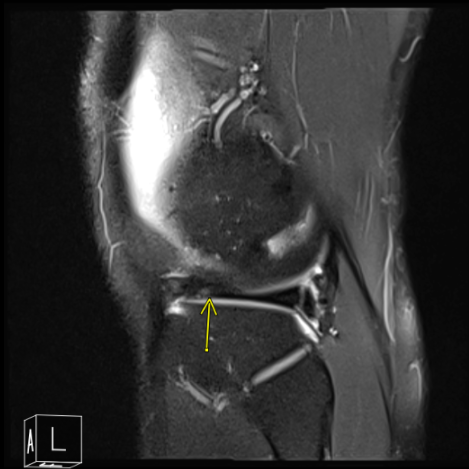

MRI of his right knee was presented and clearly showed that there is tearing of the lateral meniscus anterior horn with parameniscal cyst tracking into the anterior intercondylar notch adjacent to the anterior root attachment site measuring 2 x 2.3 x 0.8 cm. Trace right knee joint effusion.

MRI of the right knee

Patient requested to come back to the office with an MRI result. MRI impression as follows: Postsurgical changes of the lateral meniscus with mild recurrent tearing of the body segment and anterior horn however the appearance is improved compared to the presurgical study. Parameniscal cyst formation has resolved.

MRI of the right knee